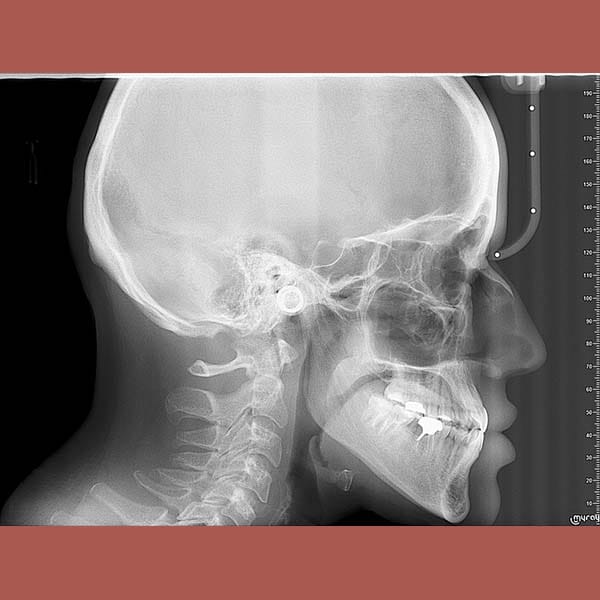

عانت هذه الشابة من بروز واضح في الذقن ناتج عن تقدم الفك السفلي، مما أثر على تناسق وجهها وسبب لها عضة معكوسة أمامية.

بعد شرح الخيارات، أوضح الدكتور خالد الكاتب أن تحسين العضة ممكن بالتقويم وحده، لكن تصحيح بروز الذقن يتطلب حلاً جذرياً. أصرت المريضة على الخيار الأفضل وهو الجراحة التقويمية. تمت الخطة على ثلاث مراحل:

كما تظهر الصور، كانت النتيجة تحولاً كاملاً. تم استعادة الشكل الطبيعي للذقن والفك السفلي، وتم تصحيح العضة المعكوسة. في النهاية، أصبح بإمكان مراجعتنا الشابة أن تستمتع بابتسامة مميزة وواثقة وملامح وجه متناغمة.